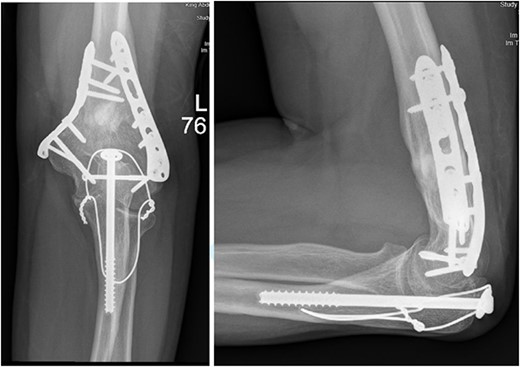

(A). Late follow-up anteroposterior (AP) view of the left elbow after ORIF. (B) Late follow-up lateral view of the left elbow after ORIF.

(A) Late follow-up anteroposterior (AP) view of the left shoulder after ORIF. (B) Late follow-up lateral scapula (Y- view) view of the left shoulder after ORIF.